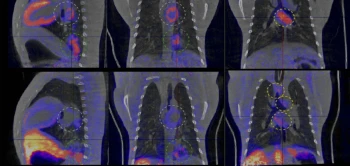

Tuberculose is nog altijd een groot wereldwijd gezondheidsprobleem. Om deze ziekte beter te kunnen bestrijden, is het belangrijk om goed te begrijpen hoe het afweersysteem van het lichaam reageert op een infectie met de tuberculosebacterie (Mycobacterium tuberculosis). Met die kennis kunnen in de toekomst betere behandelingen en/of vaccins worden ontwikkeld. In ons onderzoek hebben we gebruik gemaakt van PET-CT, een beeldvormende techniek die 3D röntgenfoto’s combineert met wat er zich in de organen afspeelt.

Met PET-CT is het mogelijk de reactie van het immuunsysteem in de longen te volgen tijdens een beginnende tuberculose-infectie bij makaken. Het voordeel van PET-CT is dat je kunt zien waar iets gebeurt, wat er gebeurt en hoe dit verandert over tijd, want we kunnen er mee in het lichaam kijken zonder te opereren.

We gebruikten voor deze studie twee PET-tracers en hebben deze met elkaar vergeleken. PET-tracers zijn radioactieve stoffen die nodig zijn om te laten zien wat er zich in de organen afspeelt.

- [18F]FDG, een veelgebruikte tracer die laat zien waar cellen veel suiker (glucose) verbruiken; wat vaak een teken van ontsteking is.

- [18F]DPA714, een nieuwere tracer die vooral bindt aan macrofagen; afweercellen die een belangrijke rol spelen bij infecties.

Uit de resultaten bleek dat beide tracers de tuberculose-infectie konden aantonen, maar op een verschillende manier. De eerste liet een toenemende ontstekingsactiviteit zien, terwijl de tweede kortdurend verhoogd was, wat wijst op een tijdelijke activatie van bepaalde immuuncellen.